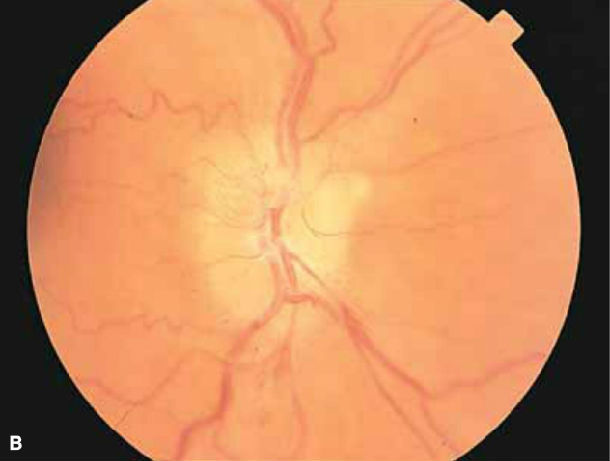

【神经眼科讨论】前部缺血性视神经病变(anterior ischemic optic

双眼非动脉炎性前部缺血性视神经病变患者

①非动脉炎性前部缺血性视神经病变(naion):中老年发病,晨起后出现无